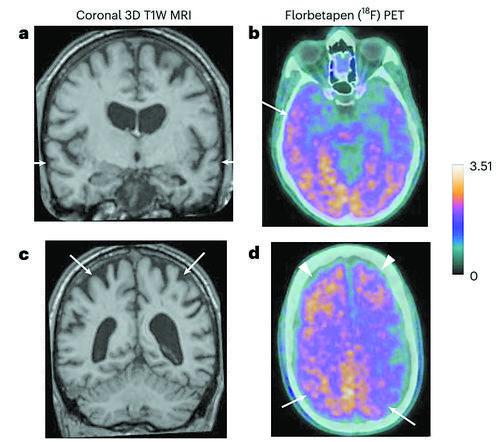

磁共振和淀粉样蛋白PET图像。图片来源:《自然·医学》

生物标志物分析在无症状时不能用于诊断阿尔茨海默病,但可以支持两名确诊患者的诊断,并表明另一人已出现阿尔茨海默病的迹象。团队还对两名研究期间去世的人做了尸检,包括大量脑组织取样,其中一名患者也显示出阿尔茨海默病的病理。